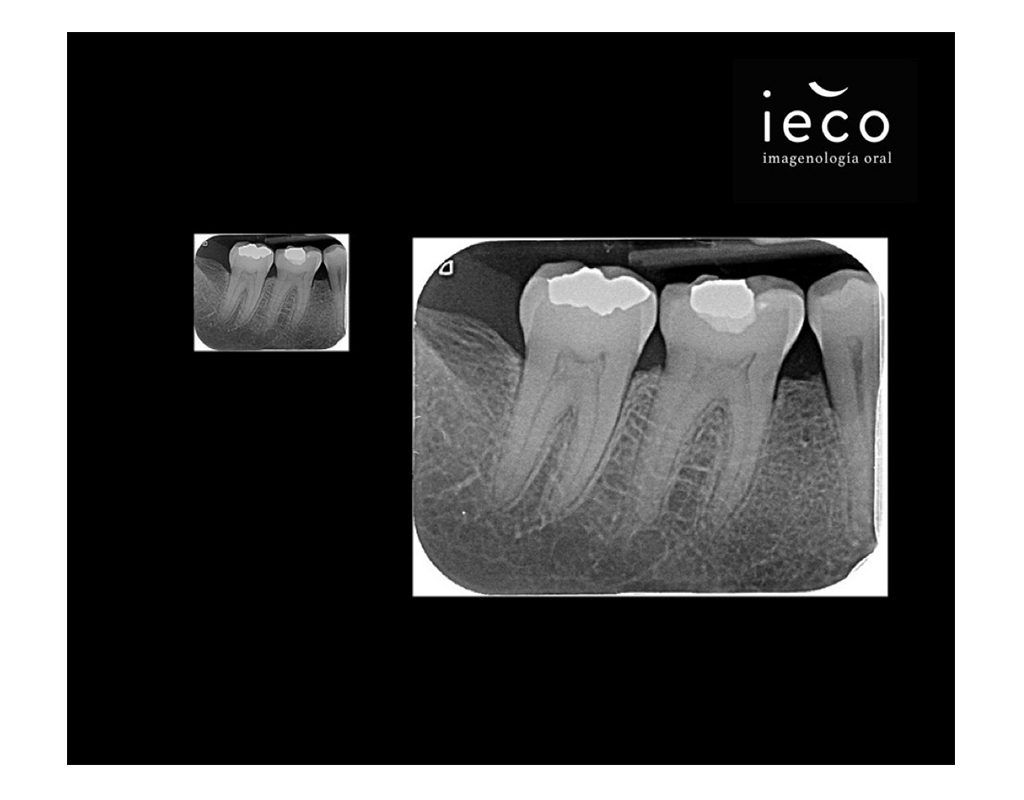

Radiografia Periapical

Es una imagen de un diente completo (Corona, raíz y tejidos circundantes), es fundamental para el diagnóstico e identificar problemas que no son visibles a simple vista.